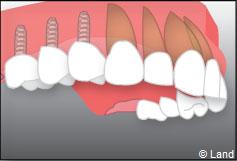

Exemple d’un implant unitaire pour remplacer une dent antérieure manquante.

Exemple de 3 dents manquantes remplacées par 3 couronnes sur implants.

Pose des piliers prothétiques et des 3 couronnes scellées.